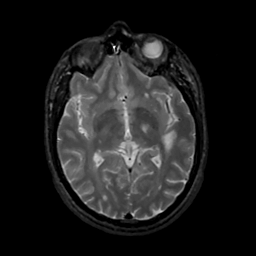

MR Study #10, April 28, 1991 -- Slice #24

[Home][Help][Clinical][Tour 1][Tour 2] Slice 24